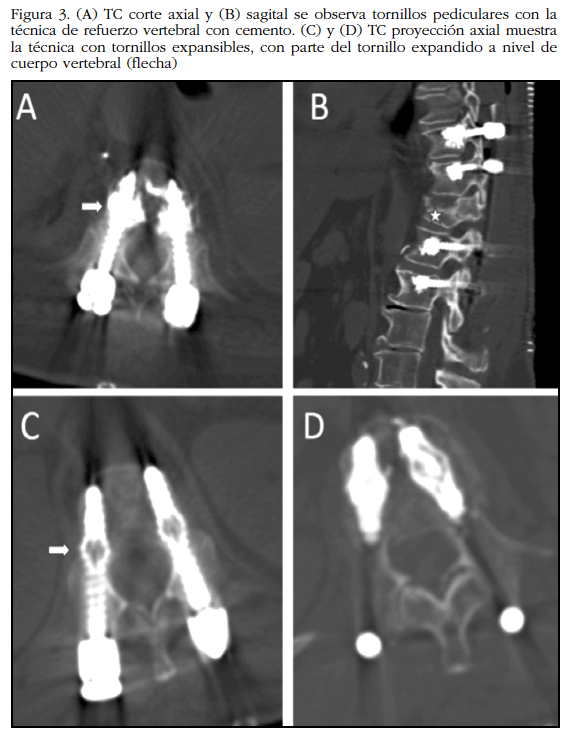

Tornillos cementados. Una técnica que ha recibido bastante atención estos últimos años consiste en el refuerzo de los tornillos pediculares a través de una capa o manto de cemento alrededor del tornillo a nivel del cuerpo vertebral; al parecer, esto distribuye la tensión del hueso trabecular adyacente de modo que sean menos propensos al aflojamiento o pullout de los tornillos 46 (Figura 3).

Este efecto se demostró más a fondo con el uso de polimetilmetacrilato (PMMA) 47: se produce un incremento entre 2 a 5 veces de la fuerza de extracción del tornillo en las vértebras osteoporóticas, hallazgo que ha sido replicado en muchos estudios. De igual manera se han utilizado otros cementos bioactivos constituidos por sulfato de calcio o fosfato de calcio con buenos resultados 48.

Tornillos pediculares expansibles. Se han probado variadas modificaciones en el diseño de tornillos para la fijación de columna vertebral osteoporótica; estos incluyen los tornillos expansibles y los tornillos recubiertos de hidroxiapatita. Los tornillos expansibles tienen un mecanismo que permite la expansión de una parte del tornillo que se encuentra dentro del cuerpo vertebral, manteniendo indemne la parte del pedículo (Figura 3). El tornillo comprime el hueso esponjoso en el cuerpo vertebral a medida que se expande, aumentando la densidad del hueso alrededor del tornillo. Se ha logrado mejorar la fijación pedicular con un aumento del 50% en la resistencia a la extracción del tornillo en el hueso osteoporótico 50. Este efecto se magnificó cuando se reforzó el tornillo expansible con cemento óseo 51) (52. Un inconveniente de esta técnica es la dificultad que implican las cirugías de revisión que requieren la extracción de los tornillos expansibles.